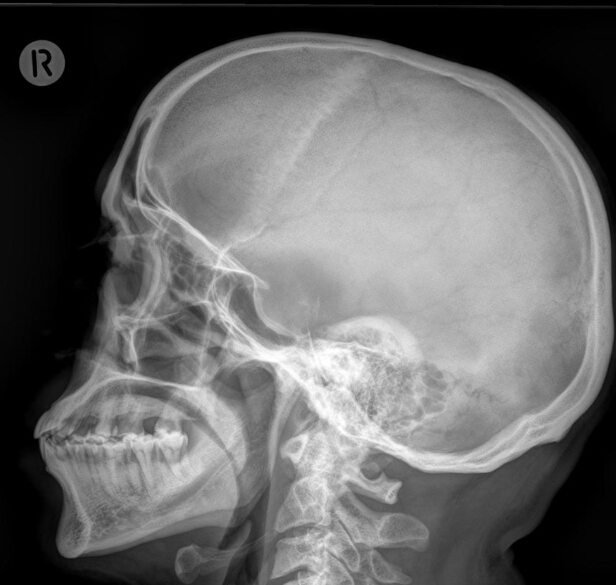

What is the radiographic feature? What disease is this associated with?

salt and pepper skull

HPT